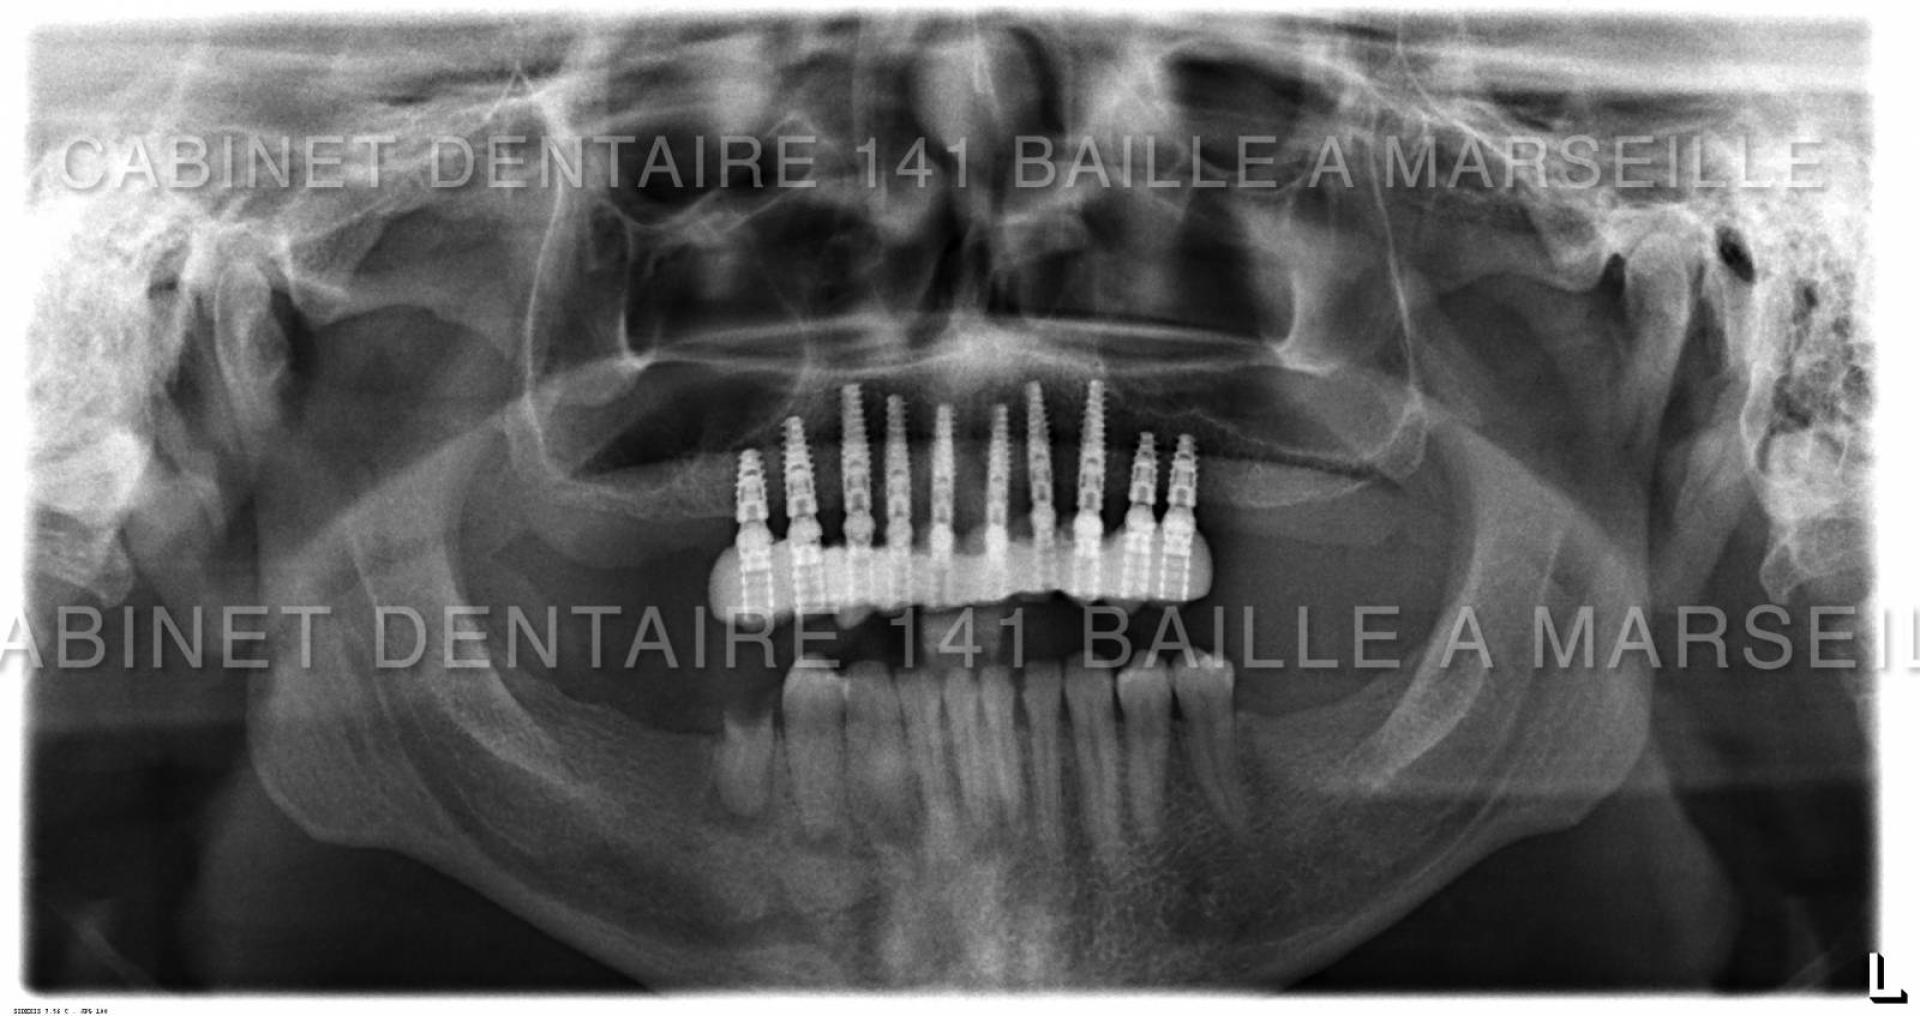

Il peut arriver qu'un patient soit obligé de remplacer toutes ses dents par des implants  dans certains cas de maladies de gencives très agressives qui entrainent une destruction de l'os support des dents .

Avant l'implantologie,ces patients n'avaient pas d'autres solutions que le port d'un appareil dentaire amovible aussi appelé par le grand public "dentier".Ces patients étaient amoindris psychologiquement car ils ressentaient le port de cette Prothèse comme un signe précoce de sénilité.De plus les appareils dentaires s'avéraient astreignants à l'usage .Ces appareils engendraient aussi un affaissement osseux rapide car l'os sous l'effet des pressions masticatoires se résorbait.

De nos jours il est possible pour ces patients d'avoir recours à des techniques implantaires appelées implantation complète en général effectuées dans la meme journée .On appelle cette technique la technique d'implantation complète avec mise en charge immédiate (MCI).

5. Placement des implants : Lors d'une chirurgie, les implants dentaires en titane seront insérés dans l'os de la mâchoire. Il faut généralement attendre quelques mois pour que l'os fusionne avec les implants (osteointégration).

6. Pose des piliers : Une fois l'osteointégration terminée, des piliers seront fixés sur les implants. Ces piliers serviront de bases pour les futures couronnes.

Ces techniques necessitent toutefois un chirurgien implantologiste qualifié et formé à ces techniques de mise en charge immédiate,d'un plateau technique complet avec bloc opératoire stérile ,prothésiste,et personnel d'assistance chirurgical qualifié.